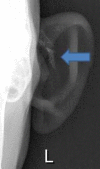

Alkaptonuria

Keywords: Alkaptonuria; Homogentisic acid; Ochronosis.